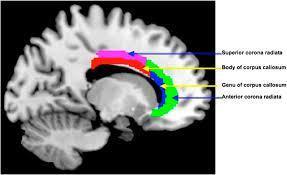

7. Meditators use these parts of our brain when we meditate:

image from uonews.uoregon.edu

When I found this picture, it made me cry. These are the parts that hurt when I try to meditate, all lit up and obvious. I can just point and you can understand.